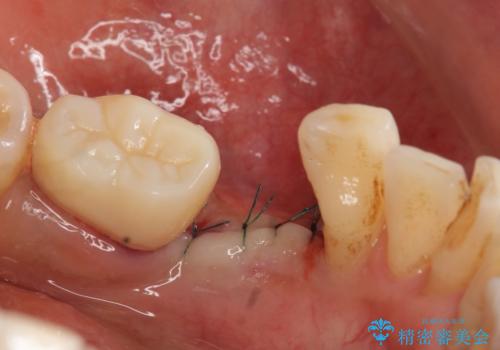

- 左下の歯並びが悪く、左側で物が咬みにくいので診て欲しいといらっしゃった方の症例です。

歯列矯正は御希望されなかったため左下4、5番目の歯を抜歯し、インプラントによる欠損補綴を行いました。

左下6も再根管治療後、オールセラミッククラウンによる補綴を行いました。

- 外科手術のため、術後に痛みや腫れ、違和感を伴います